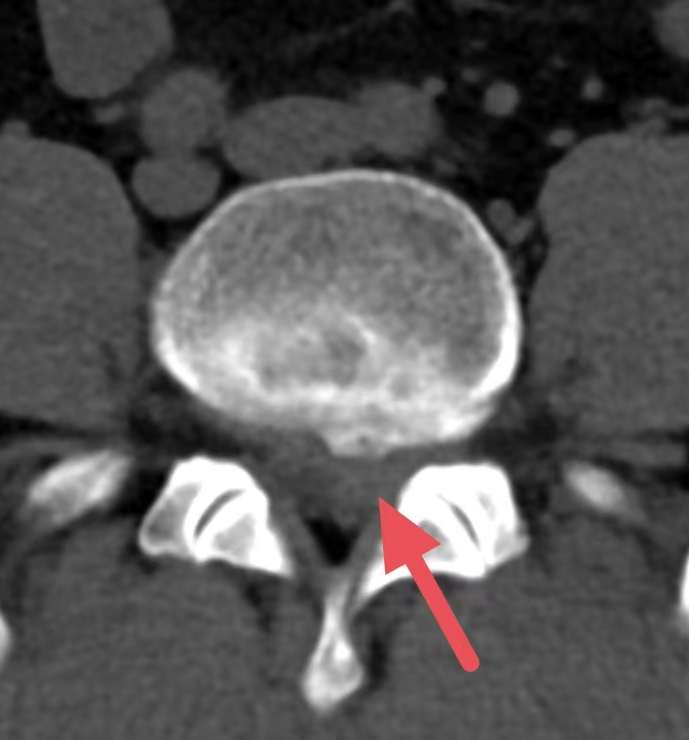

(CT影像下的腰椎间盘脱出所见)

罗某,男,47岁,因“反复腰背部左臂、左大腿疼痛1周,加重1天”入院,MR(磁共振)检查显示:L4/5椎盘膨出并左后突出,腰椎骨质增生。经专家团队讨论征求家属同意后成功开展“脊柱内镜下腰椎间盘髓核摘除术”,一周后康复出院。